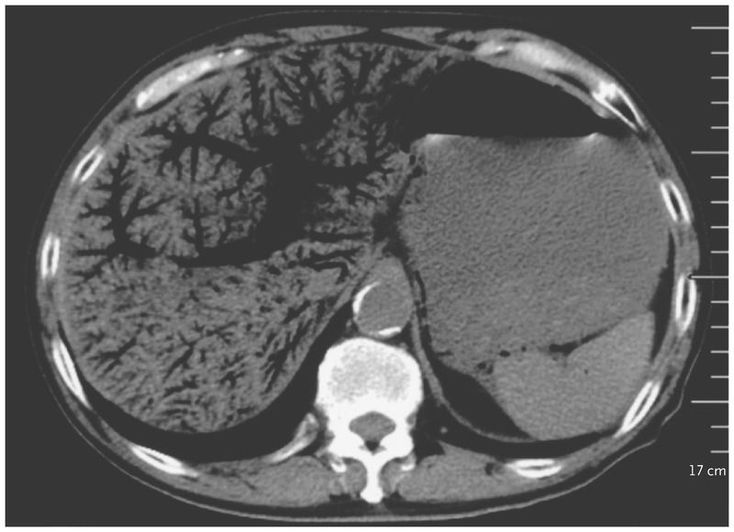

A 72-year-old man presented to the emergency department with an 11-hour history of periumbilical abdominal pain and inability to pass flatus. His medical history included chronic lymphocytic leukemia (for which he had been taking ibrutinib), type 2 diabetes, and chronic hepatitis B virus infection. The pulse was 155 beats per minute, and the blood pressure 83/52 mm Hg. On physical examination, his abdomen was diffusely tender, with the most severe pain in the right upper quadrant. Initial laboratory studies of the blood revealed a white-cell count of 22,570 per cubic millimeter (reference range, 4000 to 10,000), an arterial blood pH of 7.27 (reference range, 7.35 to 7.45), and a lactate level of 8 mmol per liter (72 mg per deciliter) (reference range, 0.5 to 1.7 mmol per liter [4.5 to 15.3 mg per deciliter]). Computed tomography of the abdomen revealed extensive portal venous gas, as well as gas in the bowel wall, which had an appearance consistent with ischemic bowel. Portal venous gas is most commonly associated with bowel ischemia and is a poor prognostic sign in patients with that condition; however, it can also develop in patients with other conditions, such as infection or inflammatory bowel disease, or as a result of an interventional procedure. Treatment was initiated with fluid resuscitation, broad-spectrum intravenous antibiotics, and vasopressors, and an urgent laparotomy was planned. However, the patient’s clinical condition deteriorated rapidly, and he died 2 hours after presentation.